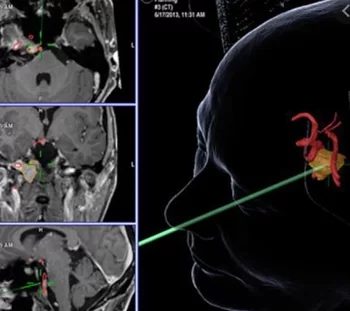

Σύγχρονες Τεχνικές

Οι σύγχρονες τεχνικές δίνουν τη δυνατότητα οι επεμβάσεις να γίνονται με μεγάλη ασφάλεια και αποτελεσματικότητα. Με την εφαρμογή τους επιτυγχάνεται το καλύτερο δυνατό αποτέλεσμα με τη μέγιστη ασφάλεια και την ελάχιστη καταπόνηση του ασθενούς.